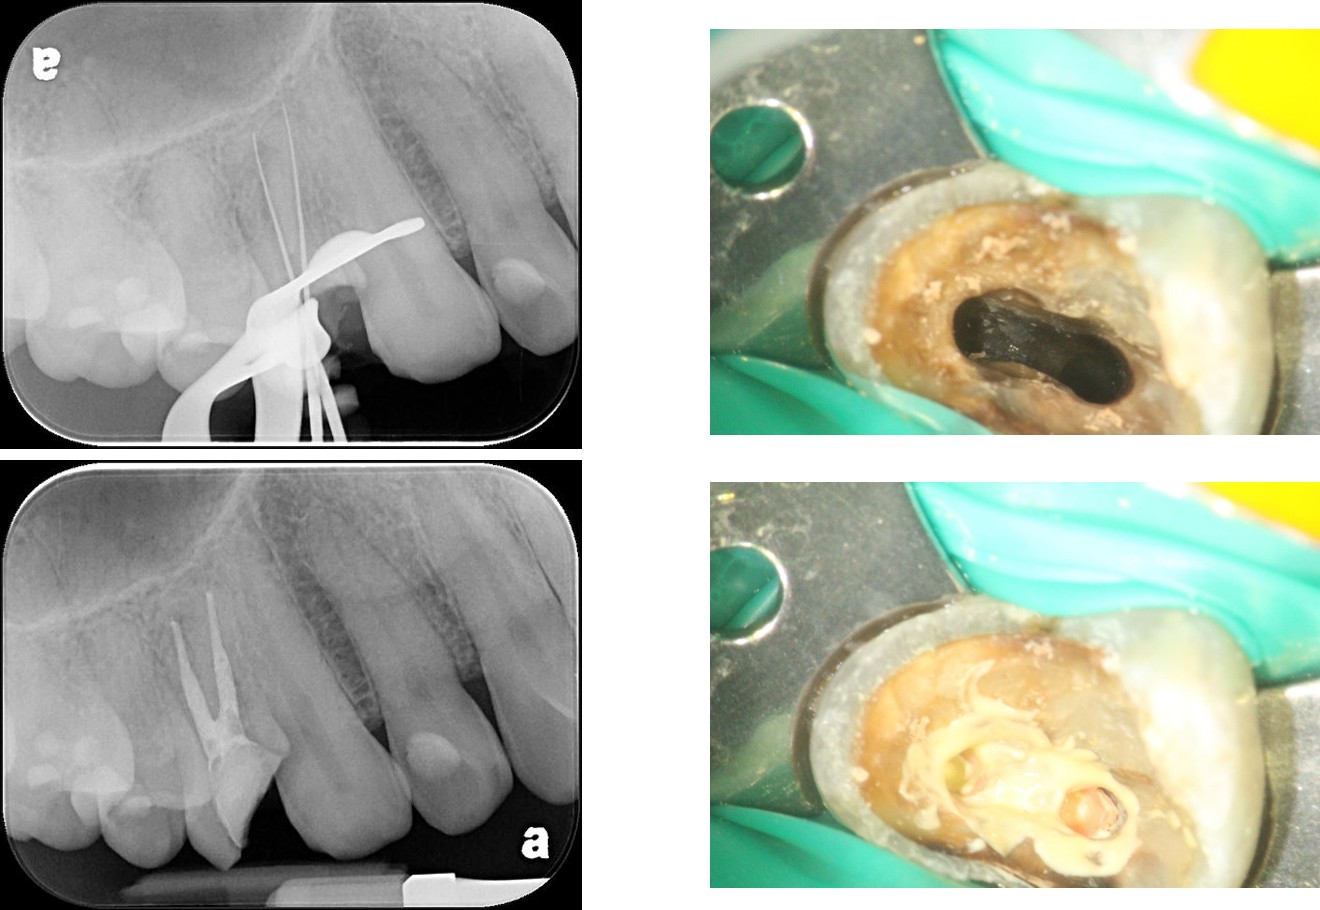

顯微根管重治療

鑄造金屬釘柱